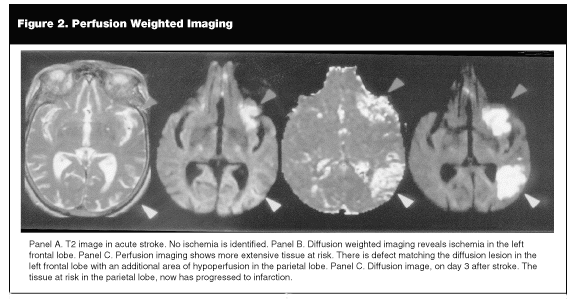

CT angiography (CTA) may be available in major centers. This technique requires an approximately 120 cc contrast injection with rapid image acquisition using a spiral (helical) scanner. CTA allows the rapid identification of occlusions in large blood vessels such as the basilar or proximal MCA. (See Figure 1.) Depending on when the passage of contrast is captured, visualization more proximally in the carotid artery or distally in MCA branches may be achieved. Disadvantages of CTA include a requirement for peripheral vascular access, possible anaphylactic reactions, and limited use in patients with renal failure.